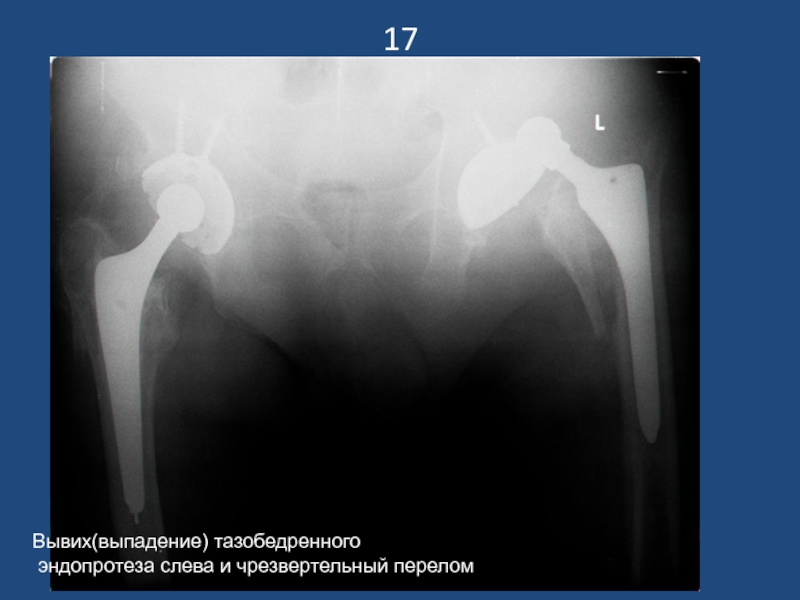

Слайд 1817

Вывих(выпадение) тазобедренного

эндопротеза слева и чрезвертельный перелом

17Вывих(выпадение) тазобедренного эндопротеза слева и чрезвертельный перелом